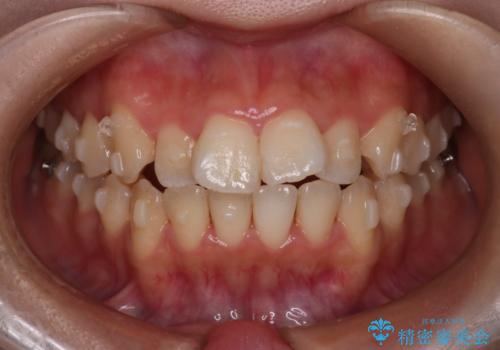

【インビザライン】マウスピースで開咬改善

- 開咬を主訴に来院されました。

IPR(歯と歯の間を削る処置)と顎間ゴムを行いながら、インビザラインで開咬を治療する計画を立てました。

治療をしながら、MFT(口腔筋機能療法)も行っていくことにしました。

歯の移動量が多いケースでしたが、患者様にマウスピースの使用とゴム掛けを頑張っていただいたので

リファイメント1回のみで治療を終わることができました。